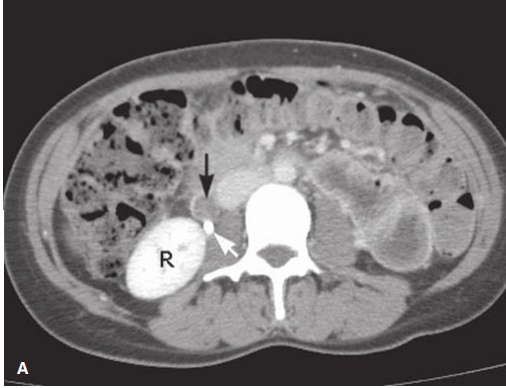

• 진단 : CT 상 thrombus 확인

• 검정색 화살표: low density의 thrombus로 채워진 확장된 ovarian vein

• 흰색 화살표: 확장된 ureter내의 조영제